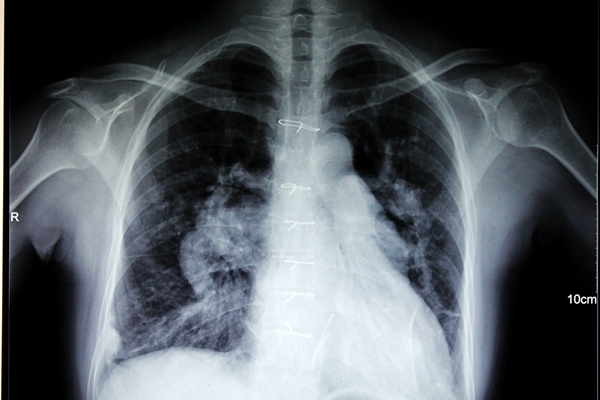

于是,12月底那场风险很大的手术中,杨柳山主任带领一支医技精湛的团队,沉着应对,为邓女士完成了房间隔缺损修补+三尖瓣成形的手术,除了三尖瓣成形这一手术中的精华部分,房间隔缺损修补还采取了活瓣修补的形式,以缓解右心房的压力。